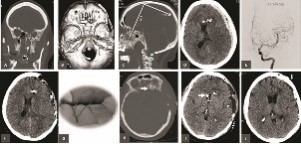

KH was a 36-year-old lady who attempted suicide following years of depression (Fig1). The slug penetrated the left orbital apex and ethmoid air-cells before tearing into the dura mater and left frontal lobe. The fragment lodged into the vertex parietal bone after ricocheting near the coronal suture. At the time of admission (May 10, 2015) she was stuporous (GCS 7, motor score 5) with frozen left-eye movements and a dilated and nonreactive pupil. There was right sided hemiparesis. Computed tomography depicted the site of penetration near left medial orbital wall, orbital roof, frontal skull base, left frontal lobe in conjunction with an acute subdural hematoma and shift of the midline structures to the right side (Fig 2, plates A, B, C, and D). Digital subtraction angiography did not reveal any vascular injury (Fig 2 plate E). An urgent decompressive hemicraniectomy was followed by CSF diversion and external ventricular drainage (Fig 2 EVD, plate F). Postoperatively, free flow of CSF and pulped brain was noticed from the soft palate and nostrils. The patient was re-explored, primarily repairing the frontal base dural defect followed by reconstructing the perforation near the left orbital roof (Fig 2 plates G, H). Six weeks following her pTBI injury the patient had autologous cranioplasty (Fig 2 plates I and J). Three months following pTBI she was alert and oriented but had left eye blindness and moderate weakness of right foot.